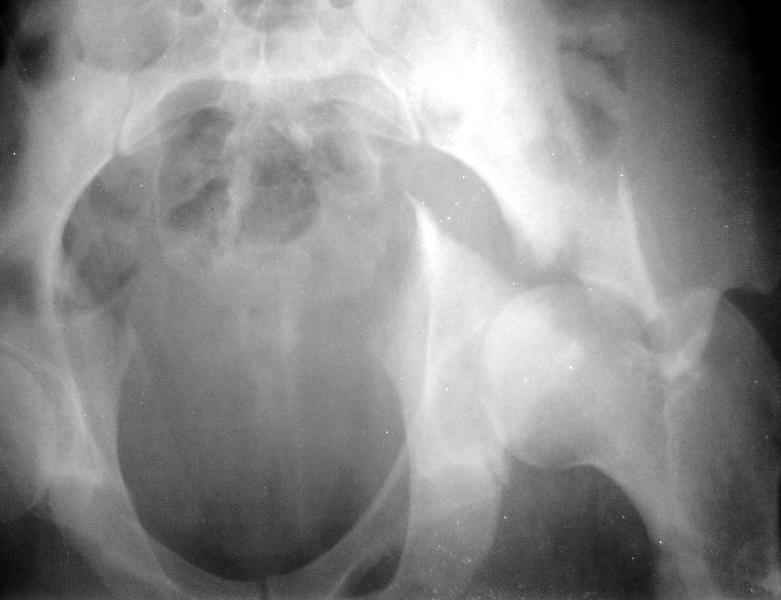

Сегодня на приеме был пациент, чьи начальный снимок напомнил обсуждаемый сейчас (см. выше). Снимки в других проекциях, показывающие истинный характер повреждения, ниже. Это inlet проекция (вход в таз) и запирательная проекция Judet.